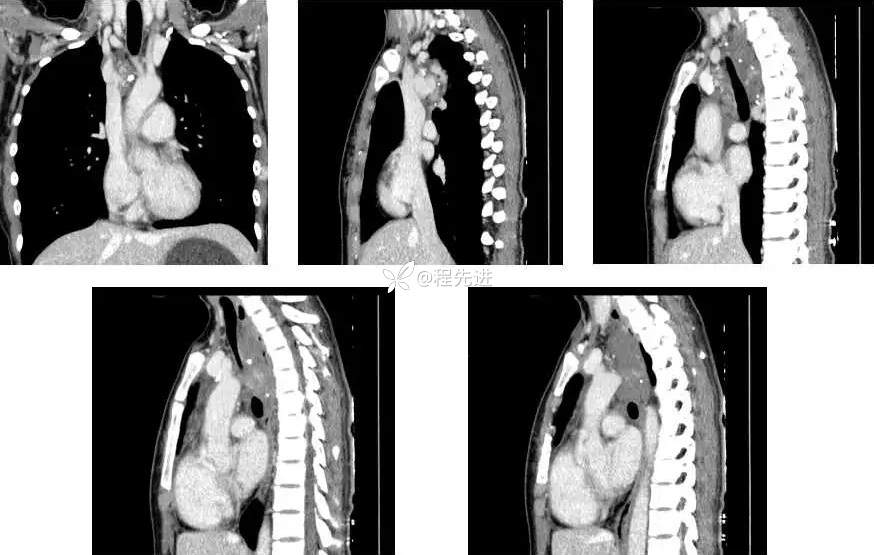

CT平扫+增强: